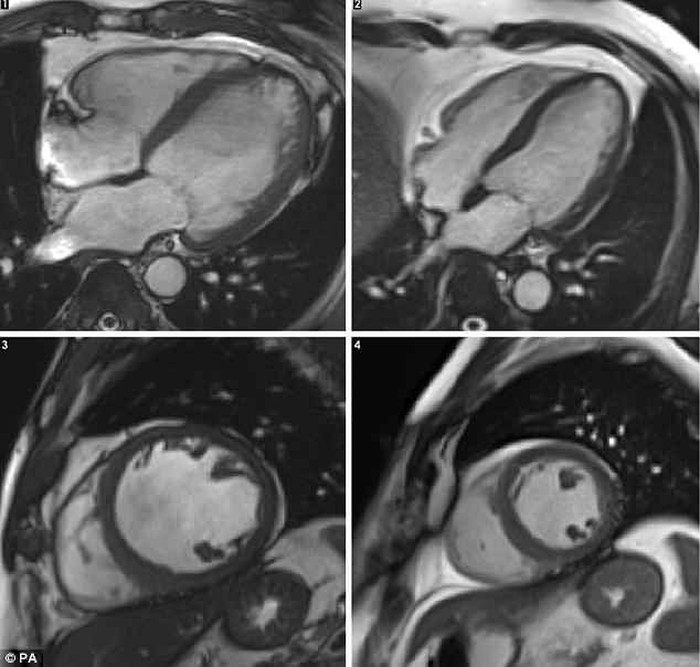

Gambar ini merupakan hasil penelitian kepada 141 pasien alcoholic cardiomyopathy (ACM) di Inggris. Ditemukan bahwa berdasarkan pemindaian, jantung orang yang doyan mengonsumsi alkohol terlihat lebih besar karena mengalami pembengkakan.

dr Ware mengatakan alkohol mempercepat perubahan bentuk jantung. Konsumsi alkohol membuat otot jantung menebal dan jaringannya menjadi tipis dan melar.

Akibatnya, kemampuan jantung untuk memompa darah ke seluruh tubuh berkurang. Hal inilah yang membuat peminum alkohol memiliki risiko tinggi mengalami gagal jantung.